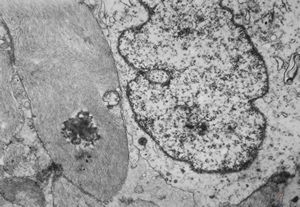

F,49y. | purulent meningitis- meningococcal v.s.

F,49y. | purulent meningitis- meningococcal v.s.

F,49y. | purulent meningitis- meningococcal v.s.